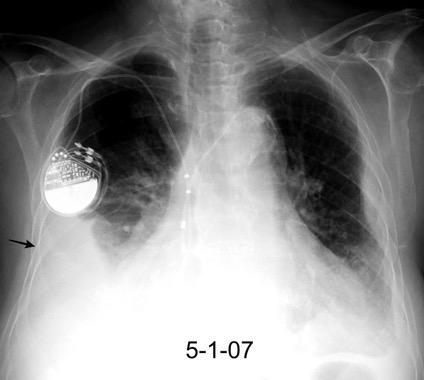

Síndrome de afectación postcardiaca (postcardiac injury)

Post infarto 1-7 % (Dressler)

Trauma cerrado Implantación marcapasos

Cirugía cardiaca. 17-31% (Post.pericardiotomía)

3707 pacientes 29 Derrames (0,78%) > de 25% del hemitórax

Todas menos 2 Izdos.

Angioplastia

By-pass coronario 21-10-03